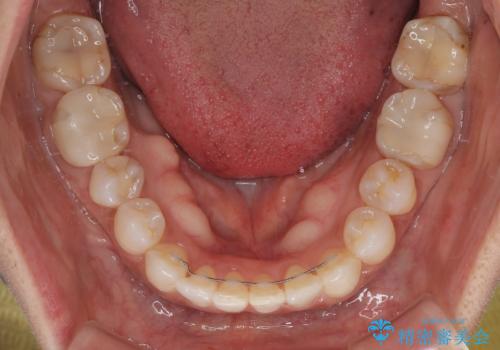

クロスバイトを治したい インビザラインによる矯正治療

咬合力による臼歯離開は顎間ゴムで改善されましたが、それとは別に下顎小臼歯がマウスピースに追従せず、補正のためのゴムかけが必要となりました。

大変なゴムかけ作業を頑張っていただき、無事に治療を終えることができました。